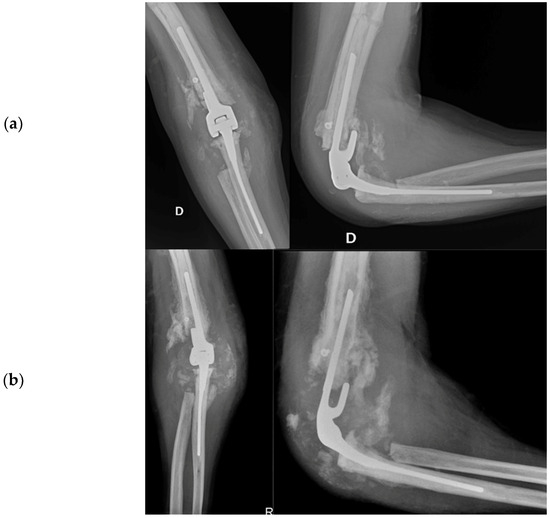

2.4.5. Total Elbow Arthroplasty

Total Elbow Arthroplasty and Complications

2.4.6. Revision Total Elbow Arthroplasty